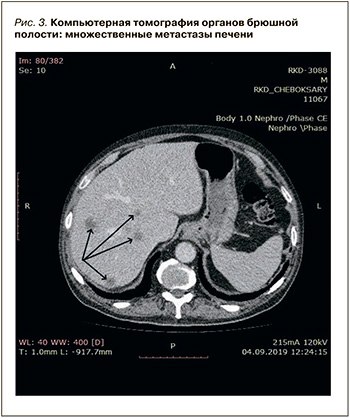

При выполнении компьютерной томографии органов брюшной полости найдено образование в хвосте поджелудочной железы с незначительным накоплением контраста и множественные метастазы в печени без увеличения лимфатических узлов (рис. 2, 3).

С учетом клинико-анамнестических, лабораторных и инструментальных данных пациенту был выставлен следующий клинический диагноз: «двусторонняя тромбоэмболия сегментарных ветвей легочной артерии промежуточно низкого риска на фоне тромбоза глубоких вен нижних конечностей и злокачественного новообразования хвоста поджелудочной железы Т3NXM1. Синдромный (панкреатогенный) сахарный диабет».